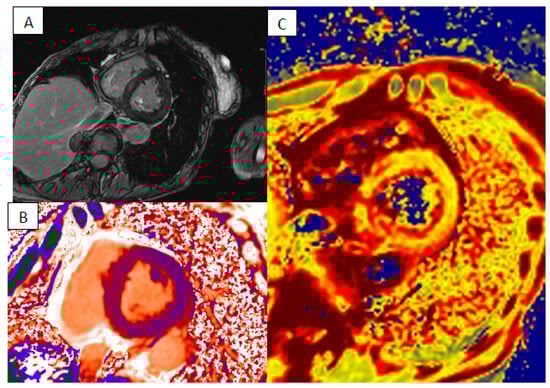

4. Cardiac Amyloidosis